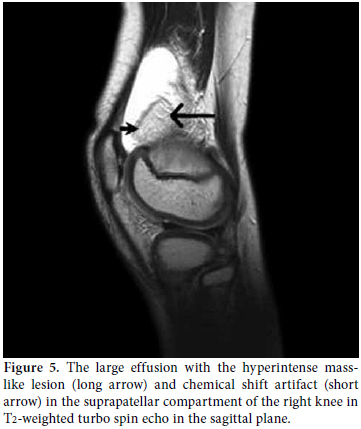

X-rays of the knees revealed minimal degenerative changes. Sonographic examination of both knees was performed by the EUB 6000 (Hitachi Medical Systems, Japan) with a high frequency linear array probe, and this revealed villous hyperechoic structures projecting into the suprapatellar effusion and a hyperechoic pseudo-mass lesion in the suprapatellar bursa in the right knee (Figure 4). Magnetic resonance imaging was performed using a 1.5 Tesla MR unit (Intera, Philips Medical Systems, the Netherlands) with an extremity coil for knee studies. The sequence included T1- and T2-weighted turbo spin echo (TSE) images in the fat-suppressed Short Tau Inversion Recovery (STIR) sequence in the axial, coronal, and sagittal planes. Magnetic resonance imaging revealed a large effusion (Figure 5), a hyperintense masslike lesion, and numerous frond-like projections in the suprapatellar compartment of the right knee (Figure 6a). The intensity of these frond-like synovial projections and the mass-like lesion, which were suppressed in the fat-saturated STIR sequences, was similar to the intensity of fat (Figure 6b). Chemical shift artifact was also detected (Figure 5). The signal intensities of these lobules were isointense with fat on the T1- and T2-weighted TSE images. These findings confirmed the fatty nature of the lesion and led us to the diagnosis of LA in the right knee. There were also mild osteochondral changes in both knees prominent in the right side. No meniscal or ligament pathology was detected in either knee.

Because of its histological nature, MR imaging findings of LA are accepted as typical and help us for a confident preoperative diagnosis. Magnetic resonance imaging is highly accurate for the identification and characterization of LA and is the best imaging modality and the cornerstone of the preoperative diagnosis.[13-15] Villous synovial proliferations with a signal intensity similar to that of fat in all sequences, mass-like subsynovial deposits, large effusions, potential demonstration of associated chemical shift artifact at the interlace of the synovial lesion and the effusion, and no evidence of hemosiderin deposition are included in the MRI results identifying LA.[1,3,5,7] These typical results allow for a confident preoperative diagnosis and can exclude other possible clinical and radiological mimickers,, such as synovial osteochondromatosis, pigmented villonodular synovitis, synovial hemangioma, and synovial lipoma.[14,15] In our cases, there was prominent suprapatellar effusion and synovial hypertrophy. In the fat-suppressed MRI, the fatty nature of the focal areas was more clearly demonstrated. Pigmented villonodular synovitis (PVNS), synovial chondromatosis, RA, intraarticular lipoma, and synovial hemangiomas should be considered in the differential diagnosis of LA as they usually present with painless synovial thickening and effusion. In PVNS, there are focal areas of hemosiderin deposits characterized by significantly low signal intensity in both T1- and T2-weighted images. There is also contrast enhancement in PVNS. Synovial chondromatosis is defined by multiple cartilaginous nodules. These nodules have intermediate-to-high signal intensity in T2-weighted images and low-tointermediate signal intensity in T1-weighted images. Synovial hemangiomas appear as either intraarticular or extraarticular lesions of intermediate signal intensity on both T1- and T2-weighted images. There might be areas of focal low signal intensity. This suggests calcified phleboliths or fluid void in abnormal vessels. Synovial lipoma is another disorder that must be considered in differential diagnosis. In this disorder, MRI reveals a solitary, localized mass of adipose tissue without synovial changes. Chronic rheumatoid arthritis shows intermediate signal intensity on T1-weighted images and relatively decreased signal intensity on T2-weighted images within the synovium. This is associated with the formation of pannus. Lipoma arborescens is usually located in the suprapatellar recess. In contrast, PVNS, synovial hemangiomatosis, and lipoma are usually located in the infrapatellar fat pad of Hoffa.[1,10,17-19] According to the clinical and radiological/laboratory examinations and the MRI findings, we concluded that LA was the correct diagnosis in our cases. Although we referred our patients to orthopedics department for surgical synovectomy aiming not only to establish LA diagnosis conclusively, but also to treat the disease, family didn’t accept the surgical synovectomy. Therefore LA diagnosis could not be confirmed histologically in our patients, though MR imaging findings were highly suggestive of LA in both cases.